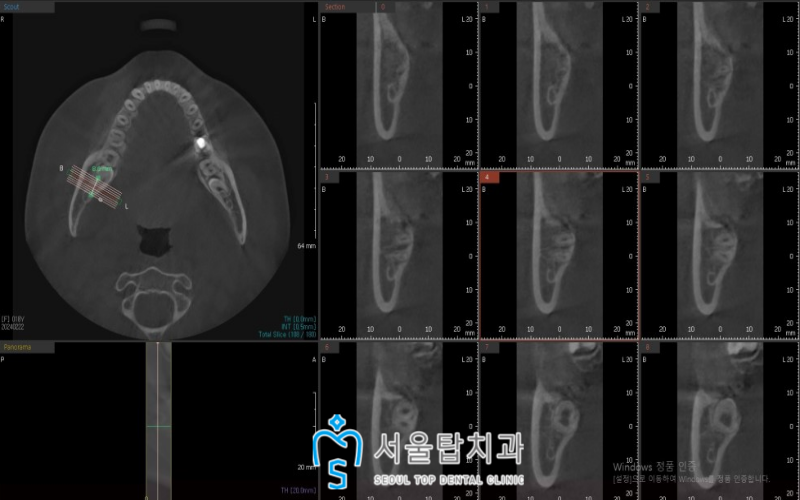

3D-CT를 촬영하여

육안으로 판단이 어려운

해부학적인 구조물까지

면밀하게 파악한 후

사랑니 발치를 진행하였습니다.

* 사랑니의 치아 뿌리 부위(노란색 표시)

* 하치조 신경관의 위치(빨간색 표시)